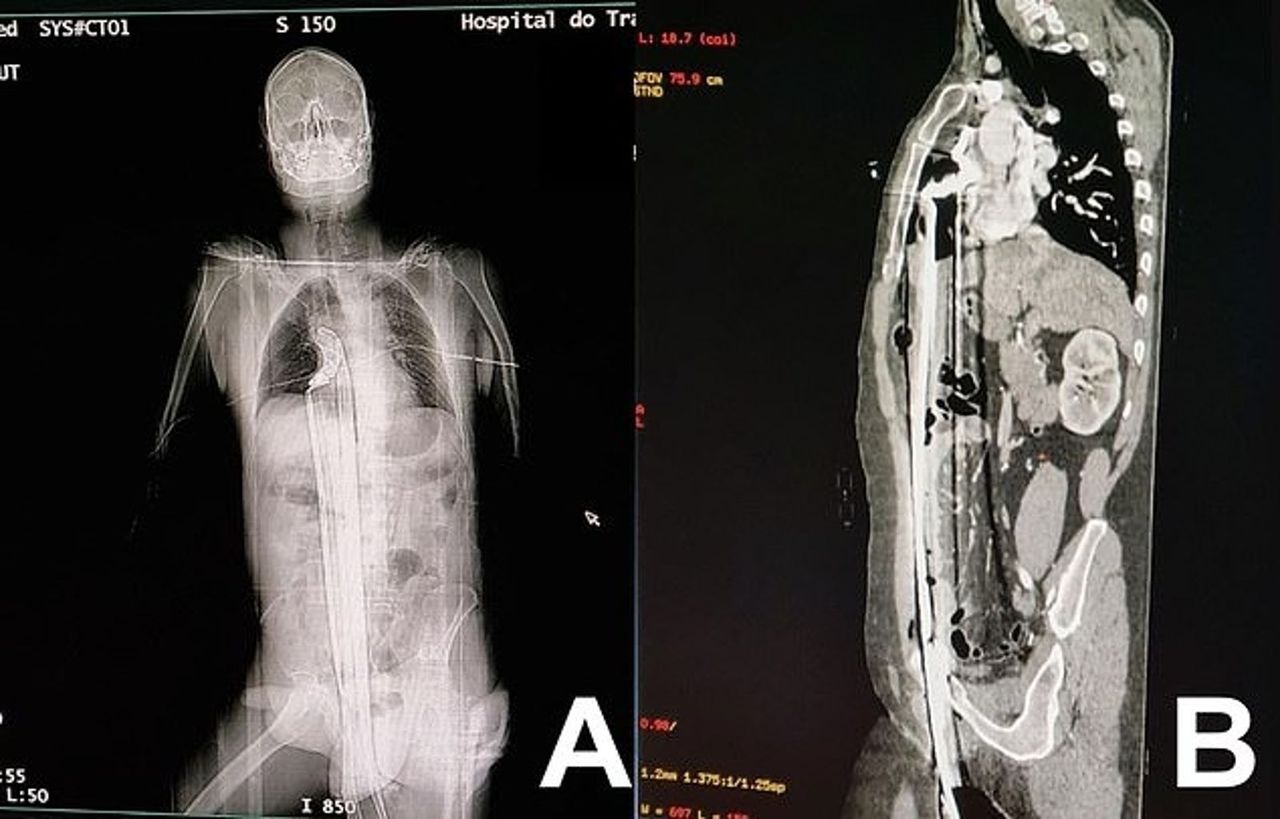

▲91公分鋼條從下體插入頂到肺!變「人肉烤串」貫穿全身,他奇蹟存活。(翻自sciencedirect.com)

巴西一個醫學團隊在最新一期《國際外科手術病例報告期刊》(International Journal of Surgery Case Reports)刊登一個奇特的病例,一名57歲男子被一條長約91公分的鋼條,從下體插入並貫穿全身,頂到肺部靠近橫膈膜的部位,但男子竟然奇蹟似地生還,而且術後復原狀況良好。

報導指出,這名男子被一條長約91公分的鋼條,從下體插入後貫穿全身,頂到橫膈膜與肺部附近部位,肝臟遭到穿刺,但閃過心臟。隨後男子被送醫急救,當他送到「Complexo Hospitalar do Trabalhador」醫院時,醫師初步檢查卻發現,男子的心率、血壓和血氧狀況,竟然都正常。

不過由於醫師研判,男子仍然處於危險狀態,於是馬上動手術。醫師剖腹後,將部分胸骨切開,從體內取出鋼條,最後將男子腹部縫合。據悉男子僅住加護病房3天,就能轉到一般病房,恢復的狀況相當良好。而且術後僅2天,男子就能下床走路與進食。